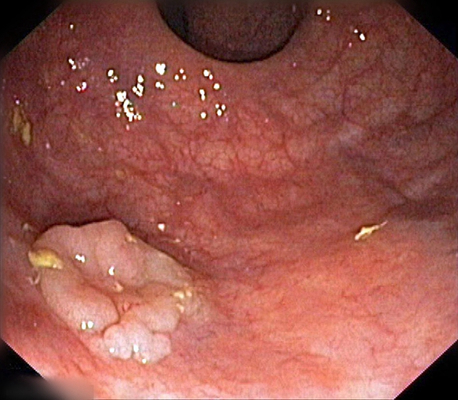

肛門癌圖片

肛癌早期症狀